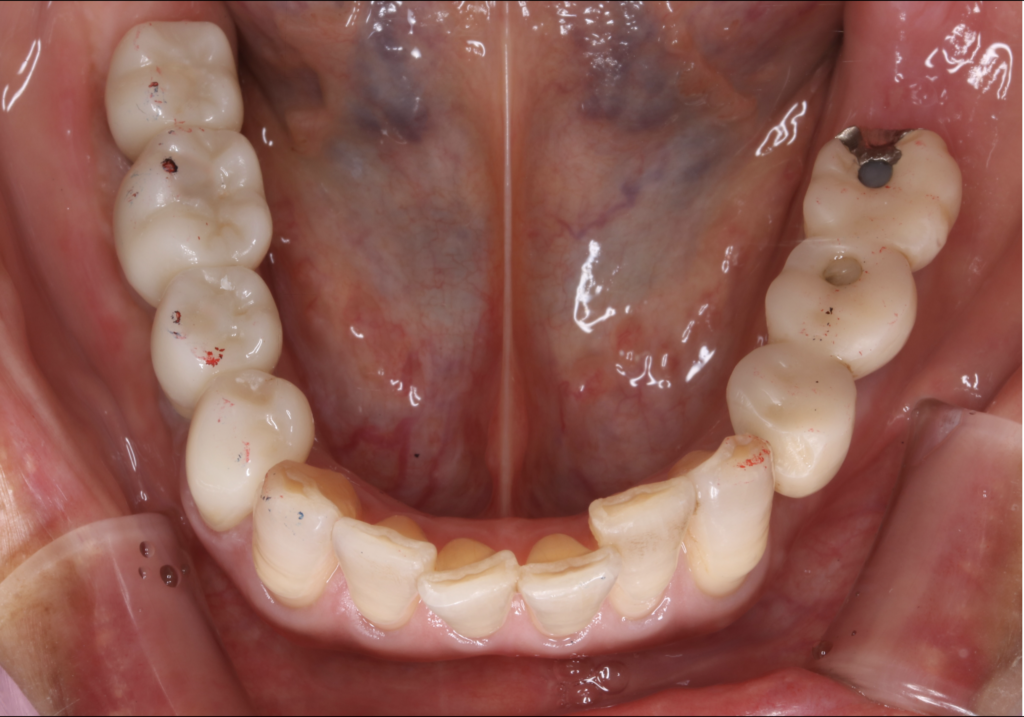

今回ご紹介する症例は、他の部位にはすでにインプラントが入っている一方で、右下には入れ歯が入っていた患者様の治療例です。

インプラントと入れ歯が混在した状態は、一見問題なく過ごせているように見えても、

長期的には噛み合わせのバランスが崩れ、周囲の歯や被せ物に負担がかかることがあります。

今回は、そうした将来的なリスクを踏まえ、

右下に3本のインプラント治療を行い、口腔内全体の安定を図った症例となります。

初診時の状態と主訴:

患者様は、

「右下の入れ歯と、すでに入っているインプラントとの噛み合わせが気になる」

というお悩みで当院を受診されました。

歯科的既往として、

• 他院にて複数本のインプラント治療歴あり

• 右下臼歯部は部分入れ歯を使用中

という状況でした。

日常生活に大きな支障はないものの、噛み心地の違和感や将来的な不安を感じていらっしゃいました。

診断結果:

診査・診断の結果、右下の入れ歯部位は、入れ歯自体に大きな不具合はないものの、

• 噛む力が十分に伝わらない

• インプラントが入っている反対側との噛み合わせの差

• 残っている歯や被せ物への負担

といった問題が生じやすい状態であると判断しました。

特に、インプラントと入れ歯が混在している口腔内では、長期的にみて噛み合わせ全体が不安定になりやすく、

周囲の歯が壊れてしまうリスクが高くなります。